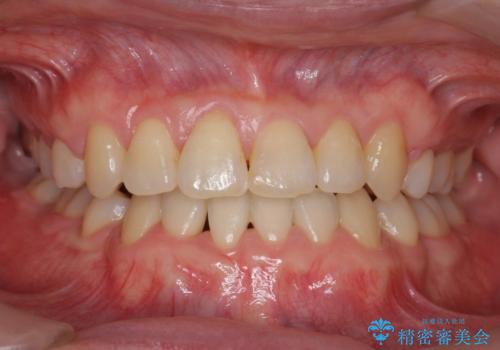

- 受け口を主訴に来院。

下あごが大きく、顎の手術を含めた矯正をおすすめしましたが、手術は怖いので絶対にしたくないとのことでした。

歯並びのみを治す矯正は難しく、長期にわたる治療になるとご説明しました。

かみしめもあり、骨も固く、歯根も長いためなかなか歯が動かず、患者様も治療する側も忍耐を要する長期戦となりました。